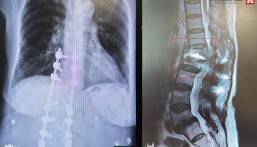

تمكن مستشفى الدكتور سليمان الحبيب بالخبر، من إجراء جراحة ناجحة لإنقاذ عين مراجعة تبلغ من العمر 28 عاماً، كانت قد أجرت سابقاً عملية شبكية بالعين اليسرى ولم تتكلل بالنجاح، وعانت بعدها من الفقدان التام للنظر مع تجمع شديد للصديد داخل مقلة العين. الأمر الذي يمثل خطورة على حياتها حال انتقال الصديد للدماغ لاسمح الله. ذكر ذلك الدكتور يحيى كريري استشاري طب وجراحة العيون رئيس الفريق الطبي المعالج الحاصل على الزمالة في طب وجراحة الشبكية.

وقال الدكتور كريري أنه فور وصول المراجعة للعيادة تم الإستماع إلى شكواها والإطلاع على ملفها الطبي، وتبين أنها تعاني من آلام شديدة بالعين اليسرى، وتورم مع تشوه في شكل العين، نتيجة تجمع السوائل بداخلها، موضحاً بأنه تم إخضاعها لفحوصات طبية دقيقة، شملت التصوير المقطعي (C.T Scan) وأشعة الموجات فوق الصوتية (Ultrasound) وعدداً من التحاليل المخبرية، بالإضافة إلى أخذ عينة من سوائل العين، وقد بينت النتائج وجود التهاب بكتيري شديد، وانتشار للصديد مع إصابة جزء بسيط من العين بالتليف، الأمر الذي قد يتسبب في فقدان العين بصورة نهائية في حال التأخر بالعلاج.

مفيدأً بأنه بعد دراسة الفريق الطبي لكافة معطيات النتائج، وضعت خطة علاجية دقيقة، تبدأ بإخضاع المراجعة للعلاج المناعي قبل وبعد العملية، ومن ثم التدخل الجراحي، مشيراً إلى أن الجراحة استغرقت ساعتين تحت التخدير العام، وتم فيها الاستعانة بأحدث الأجهزة تطوراً والمعروف بأسم “Constellation”، والذي ساعد في شفط كامل الصديد والسوائل المتراكمة بالعين بشكل آمن، ومن ثم عمل إصلاح وترميم للجزء المتليف، تبعها حقن زيت السيليكون، للمساعدة في الحفاظ على محتوى العين، وكذلك التأكد من عدم انتشار الصديد داخل الدماغ، نقلت بعدها المراجعة إلى جناح التنويم.

وأفاد الدكتور كريري أن جهود الفريق الطبي المعالج تكللت بالنجاح ولله الحمد، حيث تلاشت الآلام بصورة تدريجية بعد العملية مباشرة، ومن ثم استطاعت المراجعة الابصار بالعين مجدداً وعاد حجم العين لشكله الطبيعي، وقد خرجت من المستشفى بعد 48 ساعة وهي بصحة جيدة.